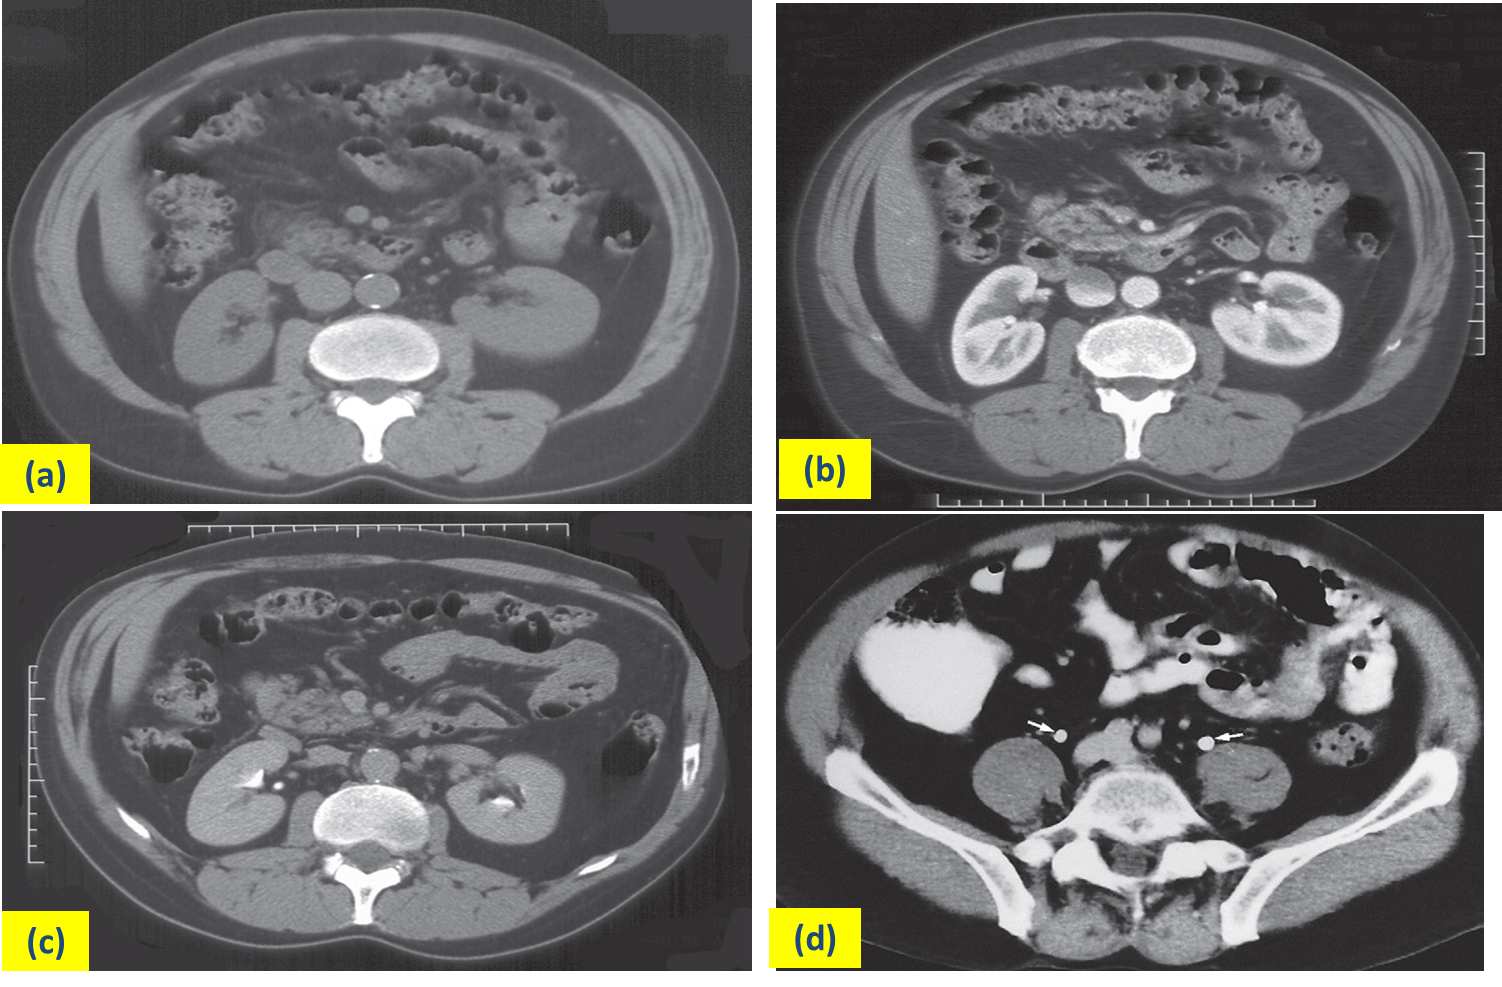

Normal CT of kidneys and bladder (a)

Before the intravenous contrast has been given.

(b)Forty seconds after intravenous contrast infusion (corticomedullary phase)

(c) Ten minutes following the contrast infusion

(d) ten minutes after contrast has been given. shows Section through the pelvis showing the ureters (arrows)